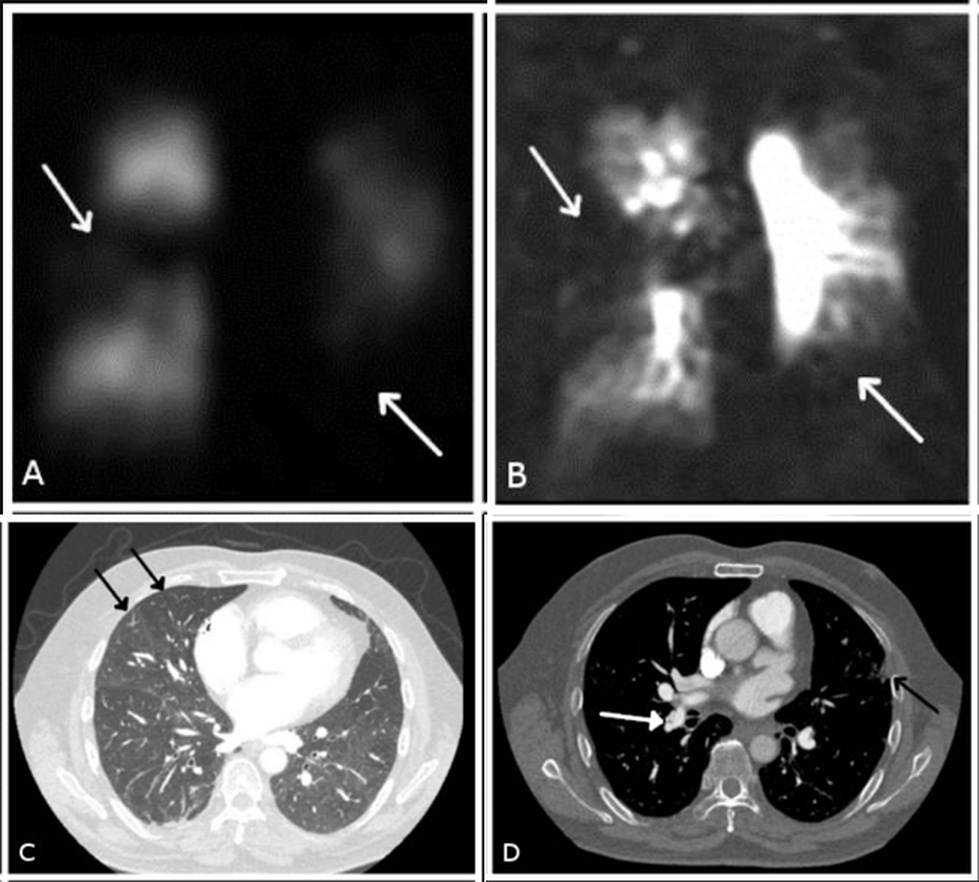

Non-invasive multi-modality imaging techniques in CTEPH are presented in Fig. 5.

Fig. 5.

Non-invasive multi-modality imaging in chronic thromboembolic disease. Bilateral segmental perfusion defects (white arrows in (A) and (B)) demonstrated on (A) planar perfusion scintigraphy, (B) 3D dynamic contrast-enhanced perfusion magnetic resonance imaging (MRI) and (C) and (D) CTPA with the typical findings of a central filling defect (web) (white arrow in (D)), mosaic perfusion pattern (black arrows in (C)) and subpleural scarring from infarction (black arrow in (D)).